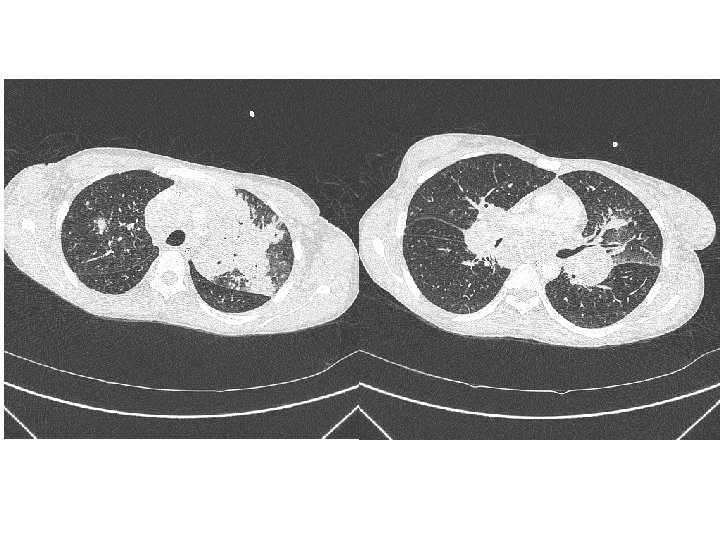

• Traitement de la tuberculose pulmonaire – Quadrithérapie débutée le 07 mai 2011 • Traitement de l’infection par le VIH – Truvada® Sustiva® le 19 mai 2011 (J 12) • Le 24 mai 2011 – Persistance de la fièvre (T=39 -41°C) – Scanner thoraco-abdomino-pelvien • Syndrome de masse ganglionnaire hilaire bilatéral sous carénaire, loge de Barety, latéro-trachéal et médiastinal • Foyer de condensation pulmonaire gauche • Transfert au CHU le 27 mai 2011